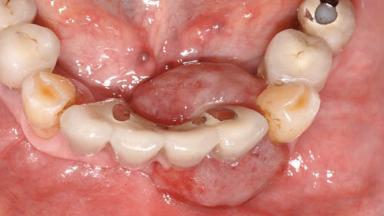

Peripheral Giant-cell Granuloma Associated with Peri-implant Tissues